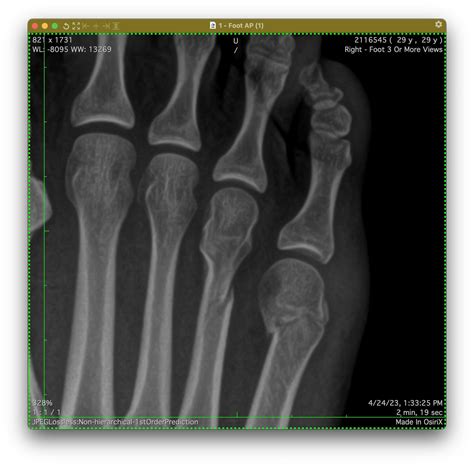

Diagnosing a Fifth Metatarsal Fracture

Diagnosing a Fifth Metatarsal Fracture typically involves a combination of physical examination and imaging tests. The diagnostic process may include:

• Physical Examination: A healthcare provider will examine the foot, checking for swelling, tenderness, and deformity.

• X-Rays: X-rays are the primary imaging tool used to confirm the presence and location of the fracture.

• CT Scans or MRIs: In some cases, more detailed imaging such as CT scans or MRIs may be required to assess the extent of the fracture and plan treatment.